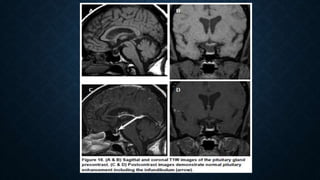

PITUITARY FOSSA • Indications: •To detect sellar and parasellar lesions. • Hormonal disturbances(hyperprolactinemia, acromegaly), • Suspected or known microadenoma or macroadenoma, • Pituitary apoplexy and sudden visual loss. • Sequences : • Routine protocol • Coronal T1SE through the sella • Post contrast T1SE with fat sat. in Sagittal and coronal plane through the sella • Post contrast T1SE with fat sat in the axial plane through the whole brain.

BRAIN MRI PROTOCOL(PITUITARY) • Coronal sequence • Plot on mediosagittal localizer superior to sella. • Slice thickness: 2mm • 2 sat. slab • Small FOV

DYNAMIC STUDY OFSELLA • Performed to evaluate cavernous sinus invasion by macroadenoma • Standard pituitary exam should be performed before the dynamic study. • FSE T1 coronal series of images is taken with a fast injecion of half dose contrast. • The injection is rapidly given at the start of the 2nd measurement. There is a 10 second pause between the first scan and the start of continuous string of post contrast measurements to prepare the injector and give a countdown.

CONTINUE • Five setsof images are obtained at 25 sec interval, with first set before contrast and the other 4 sets after contrast. • Main aim is to look for differential contrast enhancement between tumor( slow enhancement) and gland (fast enhancement).